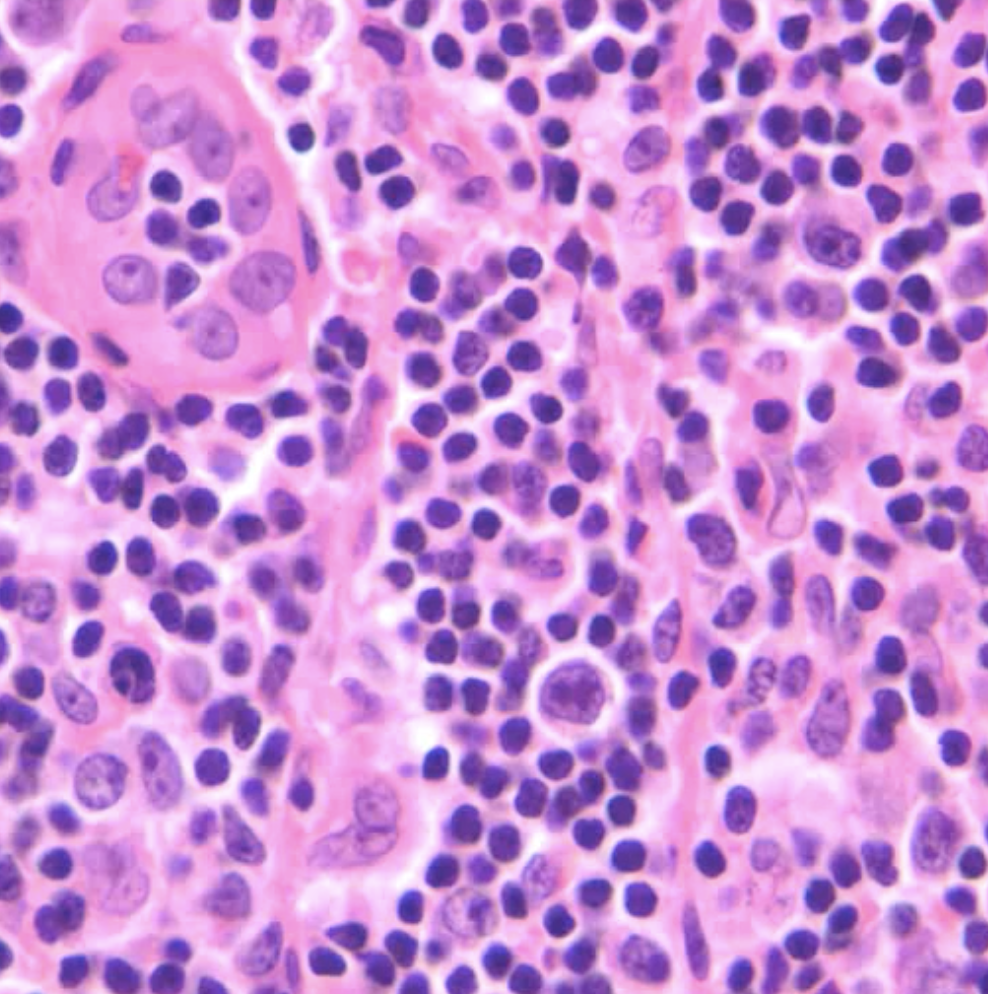

What is in the upper left hand corner of this image?

A high endothelial venule.

What is an immunoblast?

Large, activated T cells with more dispersed chromatin and large prominant nucleoli and variably vaculated cytoplasm.

They are activated helper T cells that may remain in the paracortex OR leave the node through the efferent lymphatics for effector functions.

**in this image it is in the middle but slightly down and left. Larger cell tham the lymphocytes around it**